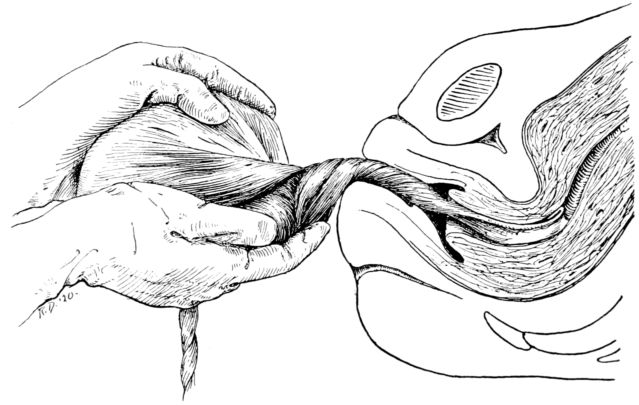

| 100. | Twisting membranes while withdrawing placenta | 281 |